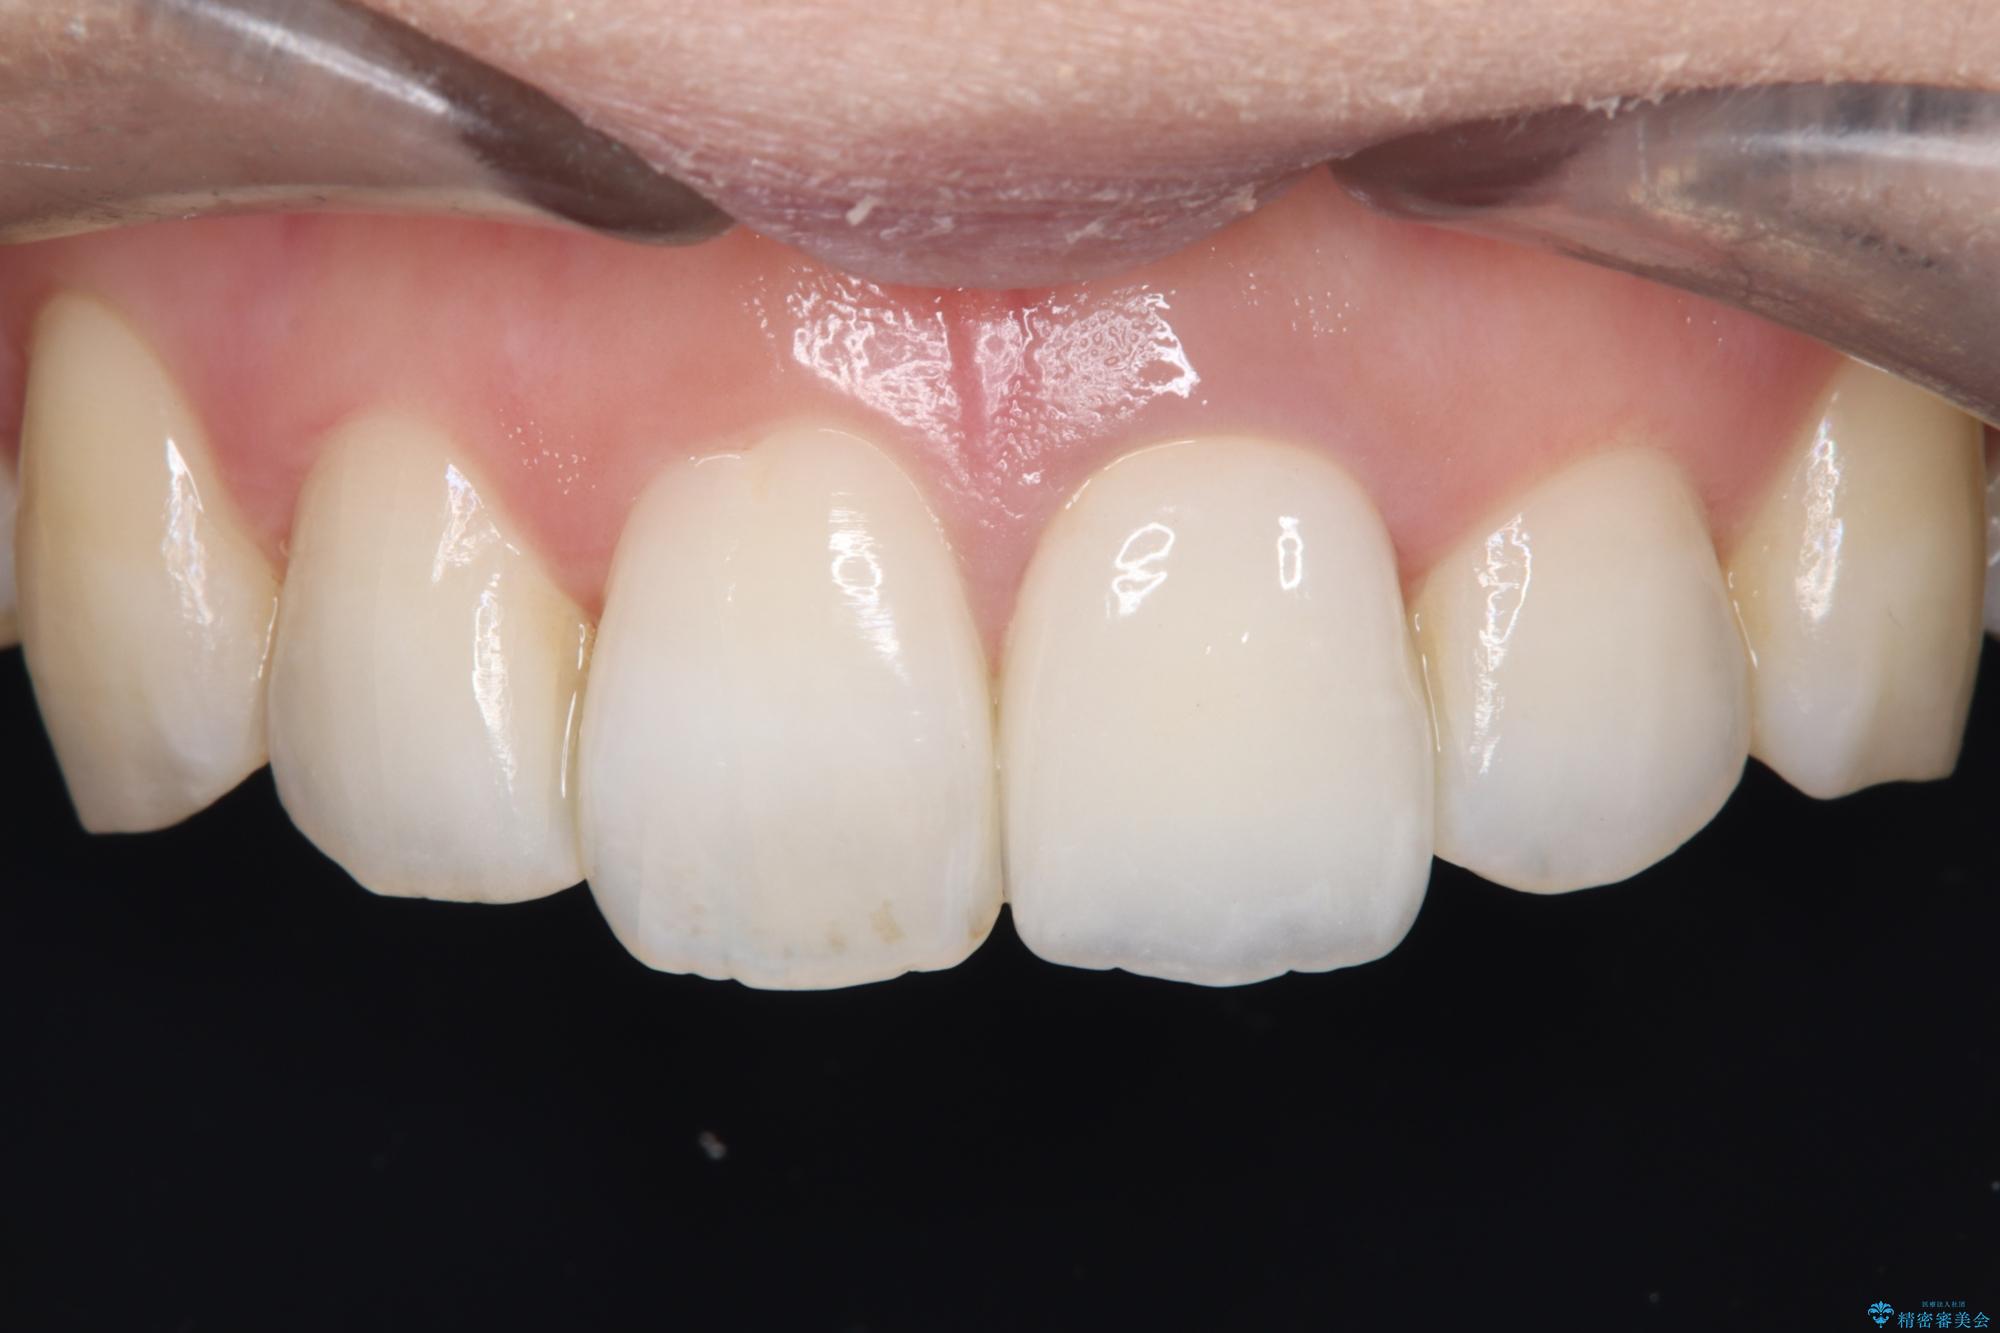

前歯の気になる変色を解消。再根管治療とオールセラミックで自然な美しさへ

オールセラミッククラウンによる修復: 最終的な被せ物には、一切の金属を使用しないオールセラミックを選択。隣の天然歯と色調や透明感を精密に合わせることで、どこを治療したかわからないほど自然な仕上がりとなりました。